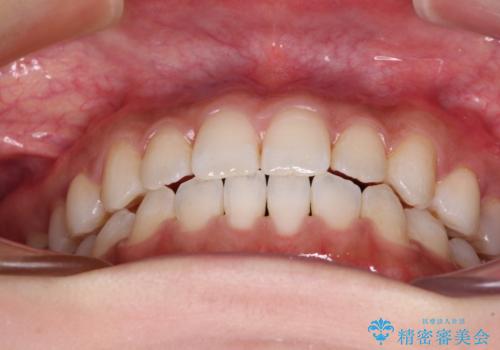

舌突出癖で口元が開いてしまう 舌トレーニングを行ったインビザライン矯正

- 前歯の上下スペースと前歯の隙間を気にして来院された患者様です。

インビザラインにより上下の前歯の隙間を閉じていくこととしました。

上下の隙間に舌が入り込むことが、すきっ歯やオープンバイトの原因であったため、舌の筋肉のトレーニングも並行して行い、後戻りの抑制を図りました。